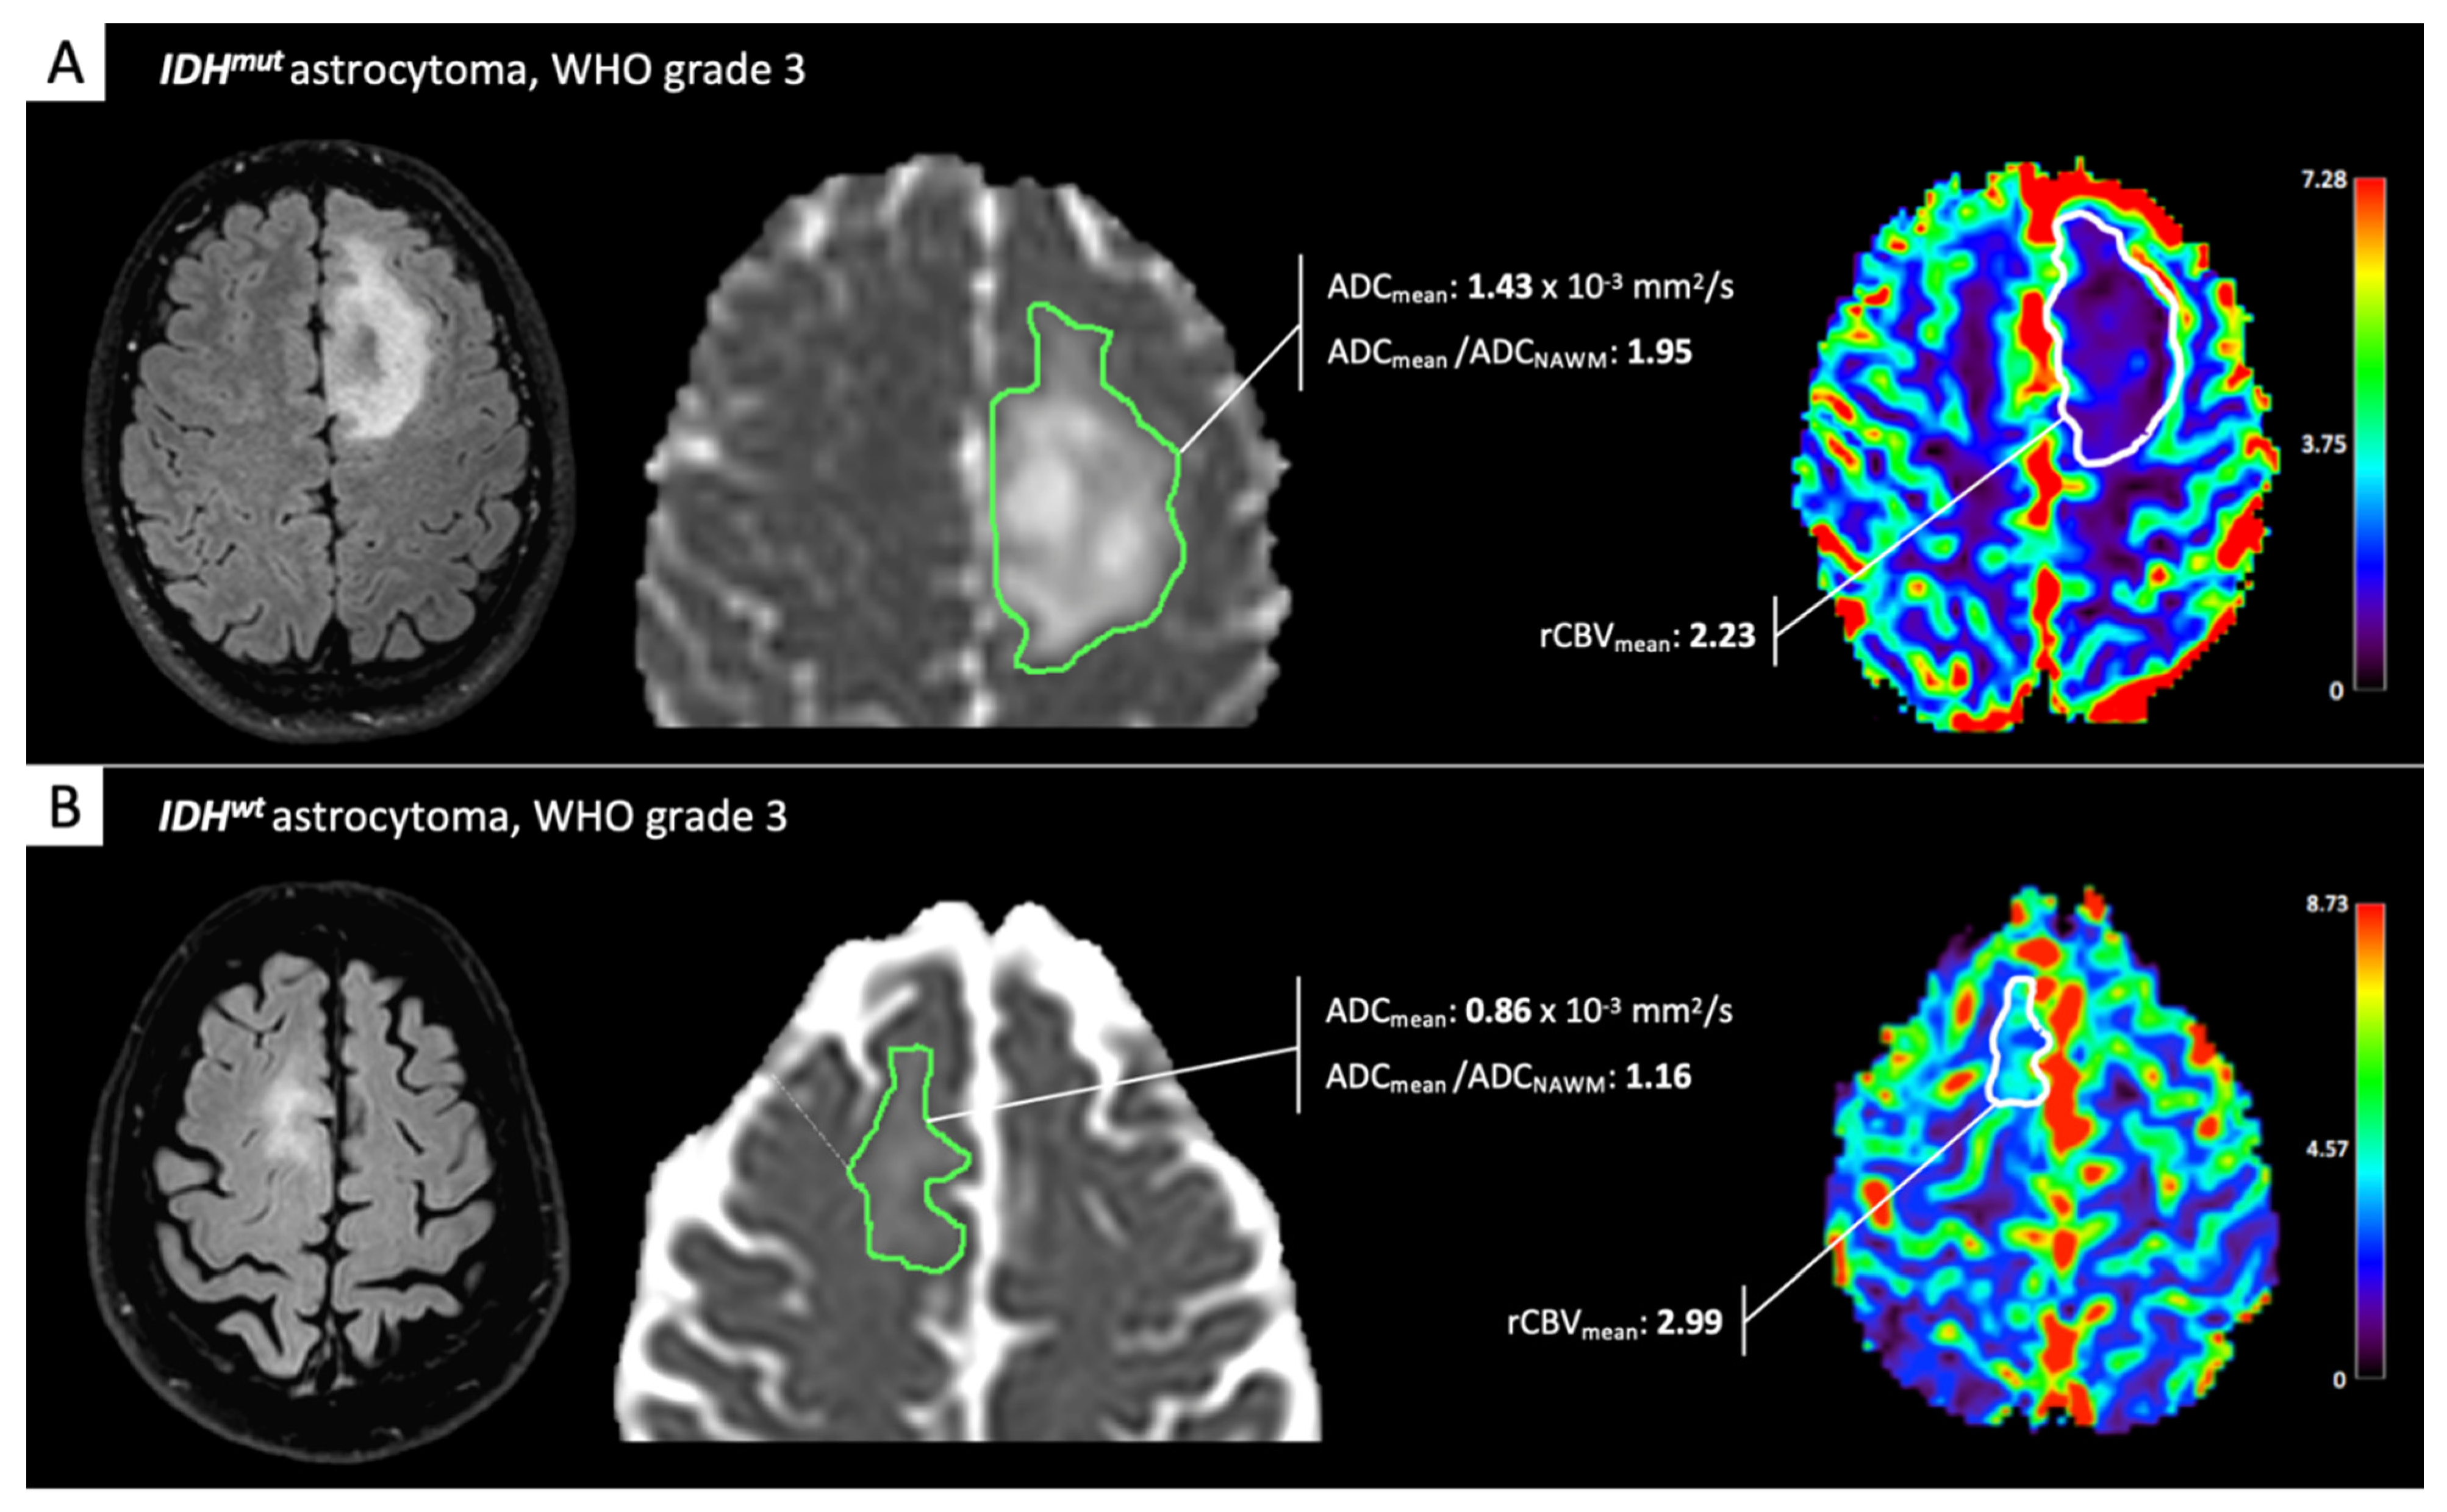

2. IDH-Status Prediction in Gliomas through Perfusion and Diffusion Assessment

- Suh, C.H.; Kim, H.S.; Jung, S.C.; Choi, C.G.; Kim, S.J. Imaging prediction of isocitrate dehydrogenase (IDH) mutation in patients with glioma: A systemic review and meta-analysis. Eur. Radiol. 2019, 29, 745–758. [Google Scholar] [CrossRef] [PubMed]

- Kickingereder, P.; Sahm, F.; Radbruch, A.; Wick, W.; Heiland, S.; Von Deimling, A.; Bendszus, M.; Wiestler, B. IDH mutation status is associated with a distinct hypoxia/angiogenesis transcriptome signature which is non-invasively predictable with rCBV imaging in human glioma. Sci. Rep. 2015, 5, 16238. [Google Scholar] [CrossRef] [PubMed]

- Lee, M.K.; Park, J.E.; Jo, Y.; Park, S.Y.; Kim, S.J.; Kim, H.S. Advanced imaging parameters improve the prediction of diffuse lower-grade gliomas subtype, IDH mutant with no 1p19q codeletion: Added value to the T2/FLAIR mismatch sign. Eur. Radiol. 2020, 30, 844–854. [Google Scholar] [CrossRef] [PubMed]

- Xing, Z.; Yang, X.; She, D.; Lin, Y.; Zhang, Y.; Cao, D. Noninvasive assessment of IDH mutational status in World Health Organization grade II and III astrocytomas using DWI and DSC-PWI combined with conventional MR imaging. Am. J. Neuroradiol. 2017, 38, 1138–1144. [Google Scholar] [CrossRef]